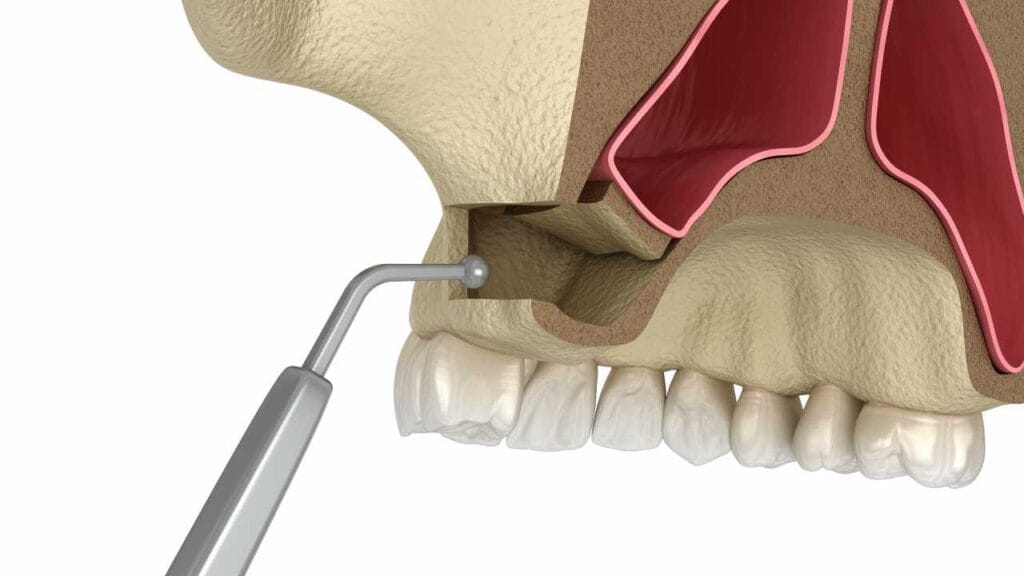

Üst çenede implant için yeterli kemik hacminin bulunmadığı durumlarda uygulanan Sinüs Lifting (Sinüs Kaldırma) operasyonu ve kemik tozu ekleme aşamalarını gösteren 3D animasyon.

Sinüs lifting ise üst çenenin arka tarafında yer alan sinüs boşluğunu (hava boşluğunu) “implant için yer açacak şekilde” kontrollü biçimde yukarı almak demektir. Bunu, evde alçıpan tavanı birkaç santim yukarı taşıyıp aydınlatma için alan açmaya benzetebilirsiniz: Amaç sinüs boşluğunu zedelemek değil, sinüs membranı (ince zar tabakası) korunarak altta yeni kemik oluşumuna yer hazırlamaktır. Bu nedenle işlem “sinüs boşluğunu genişletmek” gibi algılansa da pratikte hedef, sinüs boşluğunu güvenle kaldırıp altta kemik yüksekliği kazandırmaktır.

- Kapalı sinüs lifting, daha sınırlı bir yükseltme gerektiğinde tercih edilir. İmplant yuvasının hazırlanması sırasında, özel aletler yardımıyla sinüs tabanı kontrollü şekilde yükseltilir ve boşluğa kemik tozu eklenir. Genellikle daha “minimal” bir yaklaşımdır ve bazı vakalarda implantla aynı seansta planlanabilir.

- Açık sinüs lifting ise kemik yüksekliğinin çok daha az olduğu, daha fazla hacim artışı gerektiği durumlarda gündeme gelir. Bu yöntemde sinüsün yan duvarından kontrollü bir girişle sinüs membranı yükseltilir; oluşan alana boşluğa kemik tozu yerleştirilir ve gerekirse membranla korunur.

- Seçilen tekniğe bağlı olarak (kapalı/açık) sinüs bölgesine kontrollü erişim sağlanır.

- Sinüsün içini kaplayan membran (ince zar) korunarak yukarı doğru nazikçe yükseltilir.

- Oluşan alana, ihtiyaca göre kemik grefti (kemik tozu) yerleştirilir; bu materyal yeni kemik oluşumuna “kılavuz” olur.